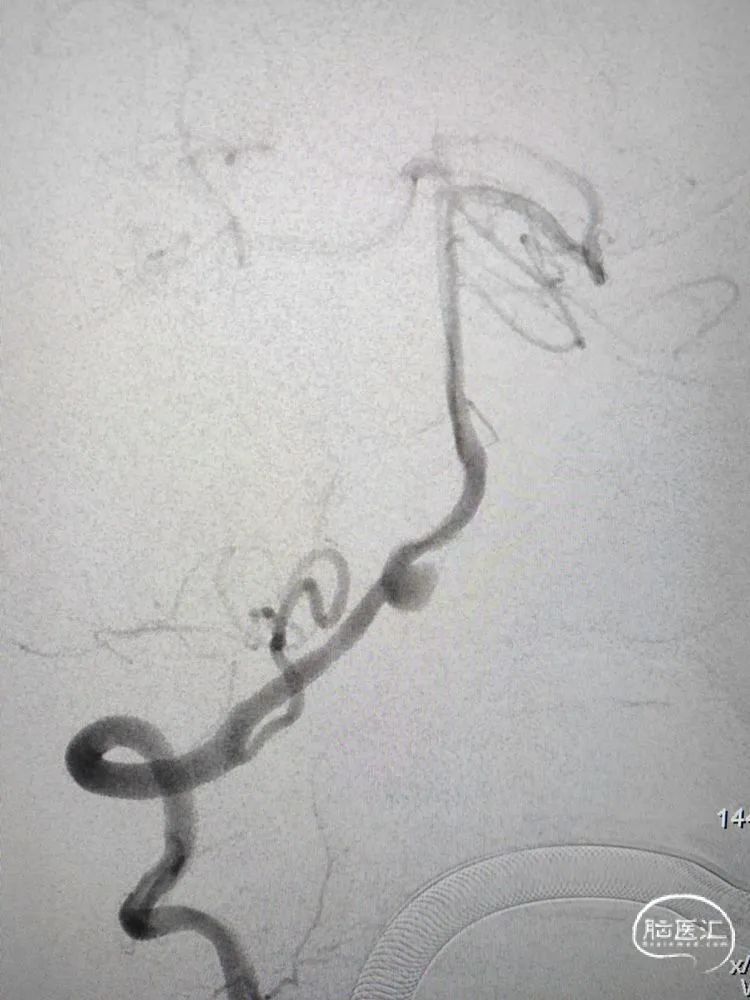

术前影像学检查:全脑血管造影检查提示右侧椎动脉V5段(颅内段)夹层动脉瘤。

动脉瘤大小约5.45mm×7.31mm,动脉瘤远端椎动脉汇合前管径约2.77mm,动脉瘤近端V4段管径约3.80mm,V5段全长约35mm,对侧椎动脉正常。

侧位造影